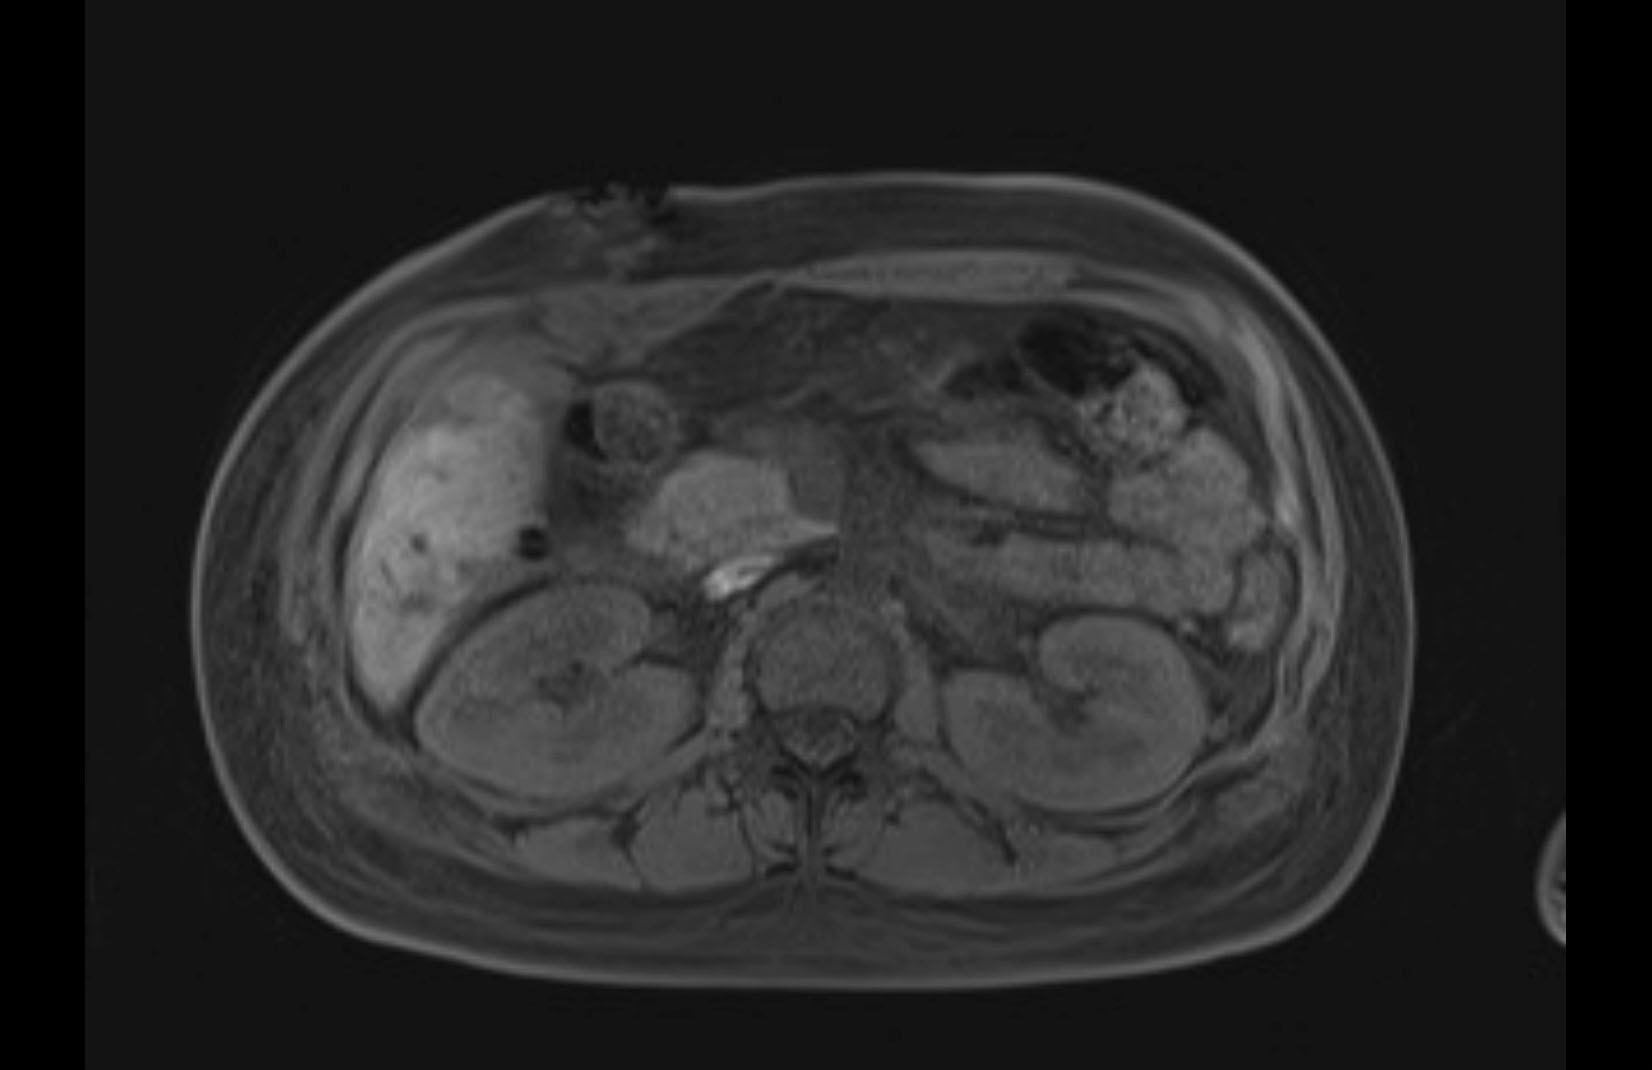

Imaging Analysis

Look through the patient's CT scan to identify any areas of concern for the necessary procedure.

MRI T1

MRI T2